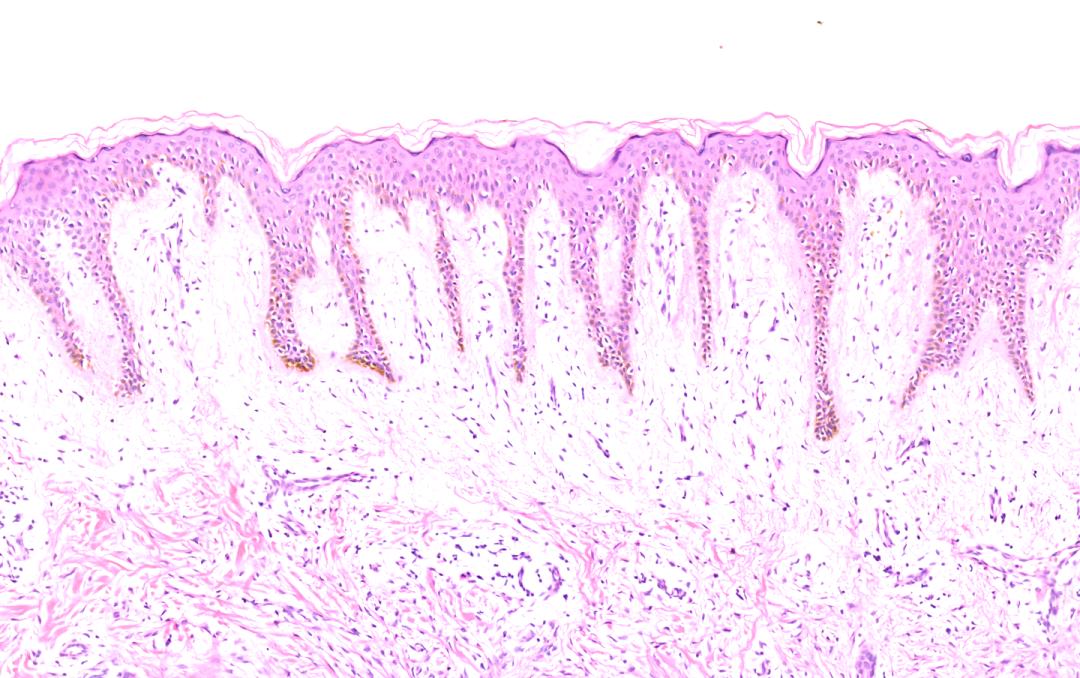

芭蕾舞会

一位皮肤纤维瘤患者的皮肤组织病理镜照片,表皮的增生像脚尖点地的芭蕾舞者们,在皮肤上,翩翩起舞。